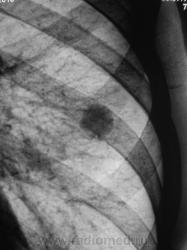

Томограммы.

Какая красивая "круглая тень"!

Ну, чем не периферический рак". А если присмотреться, так и контур полицикличен.

Или не рак?

Может и рак. А может и туберкулома. Есть снимки в динамике (за прошлые годы)?

А может гамартома...

Изображения с увеличением.

Похоже что это туберкулома. неоднородная структура?

округлое образование на фоне не изменённой легочной ткани - это гамартома

А, как насчет артерио-венозной аневризмы?

Аневризма? вряд ли...туберкулома 99%....

За 5 лет не выросло, значит добро, остальное сказать не возможно, патогномоничных симптомов гамартомы и туберкулромы, аневризмы нет

а-в мальформация?

Операция только и прояснит.

На операции - гамартома.